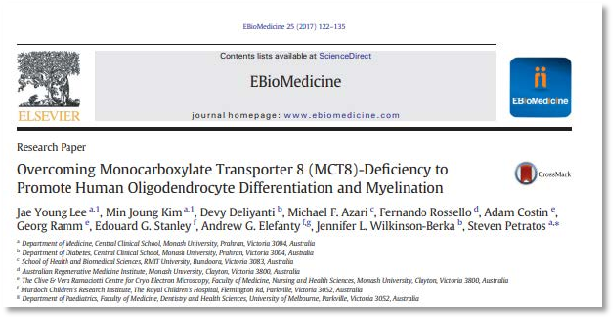

Selection of Research

Overcoming Monocarboxylate Transporter 8 (MCT8)

Thyroid Hormone Signaling in Oligodendrocytes

The iron maiden: Oligodendroglial metabolic dysfunction

Oligodendroglial Lineage Cells in Thyroid Hormone-Deprived Conditions